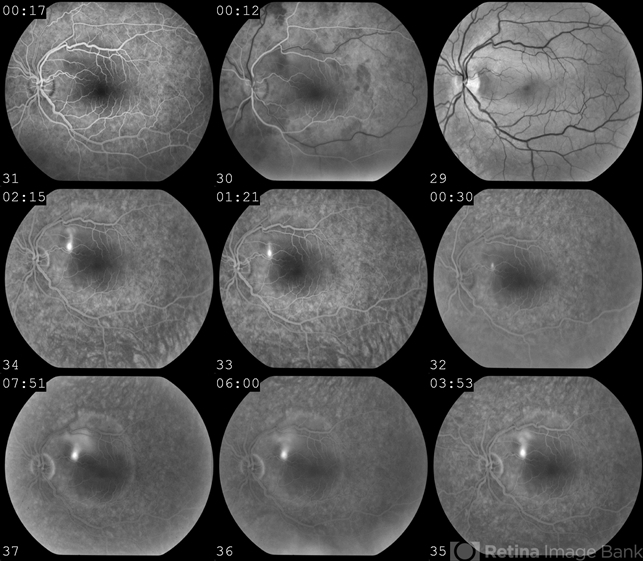

- central serous chorioretinopathy (CSCR)

- "Smoke Stack" hyperfluorescence in central serous chorioretinopathy.